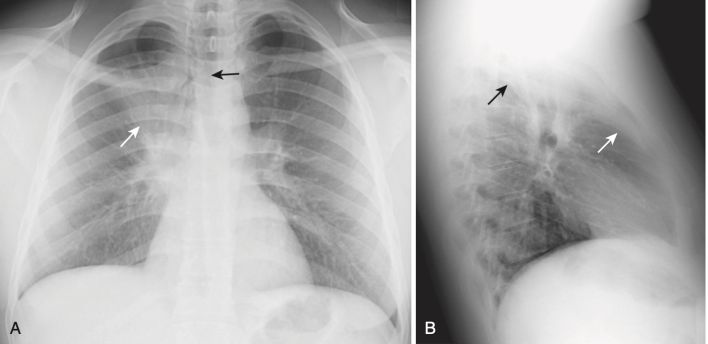

Xẹp phổi thùy trên bên phải (xem Hình 2)

- Trên phim X quang thẳng:

- Có sự dịch chuyển lên trên của rãnh liên thùy bé.

- Có sự dịch chuyển sang phải của khí quản.

- Trên phim X quang nghiêng:

- Có sự dịch chuyển lên trên của rãnh liên thùy bé và dịch chuyển về phía trước của rãnh liên thùy lớn.

- Nếu có một khối đủ lớn ở rốn phổi phải, gây xẹp phổi thùy trên bên phải, sự kết hợp của khối ở rốn phổi và sự dịch chuyển lên trên của rãnh liên thùy bé tạo ra một biểu hiện đặc trưng trên phim X quang thẳng được gọi là dấu hiệu S của Golden/S sign of Golden (Hình 11).